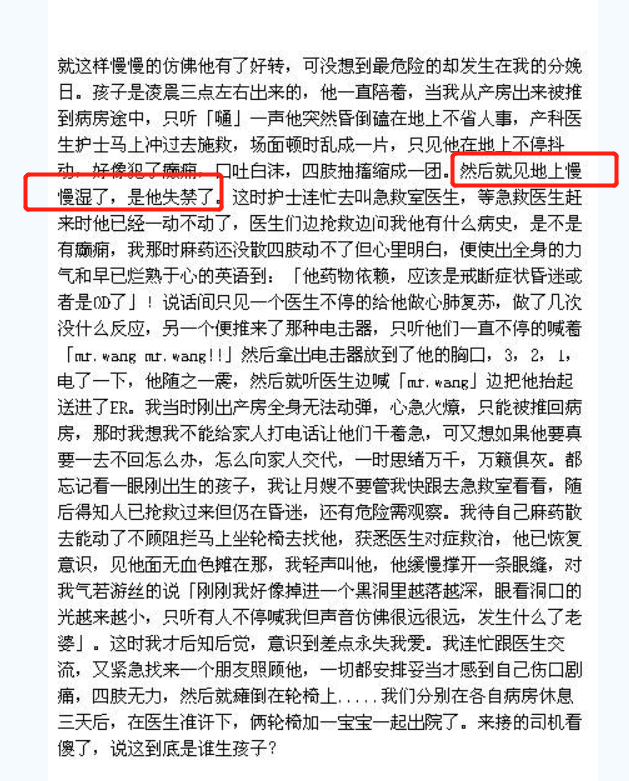

当刘涛被推出手术室送往病房时,王珂突然倒地不起,口吐白沫,四肢抽搐,没一会就小便失禁了。

看到王珂这样,刘涛再一次吓得魂飞魄散

她在慌乱之中仍然保持着最后一丝镇定,果断将自己的月嫂派去照顾王珂,随时跟自己汇报他的情况。

一度以为是癫痫发作的医生在检查之后得知,这是药物的戒断反应。

由于刘涛生产,休息不好的王珂长时间滴水未进,这才诱发了病情。

虽然在临床上的死亡率高达50%,但好在如今已经安然无恙了。

里面还提到了王珂大小便失禁的事。

在常人眼里,这种细枝末节的透露无疑会让曾经作为“京城四少”的王珂颜面尽失。

但是令人意外的是,王珂转发了微博,还自嘲道:以后尽量不尿一地,麻烦保洁阿姨了,用自己的方式为爱妻加油。